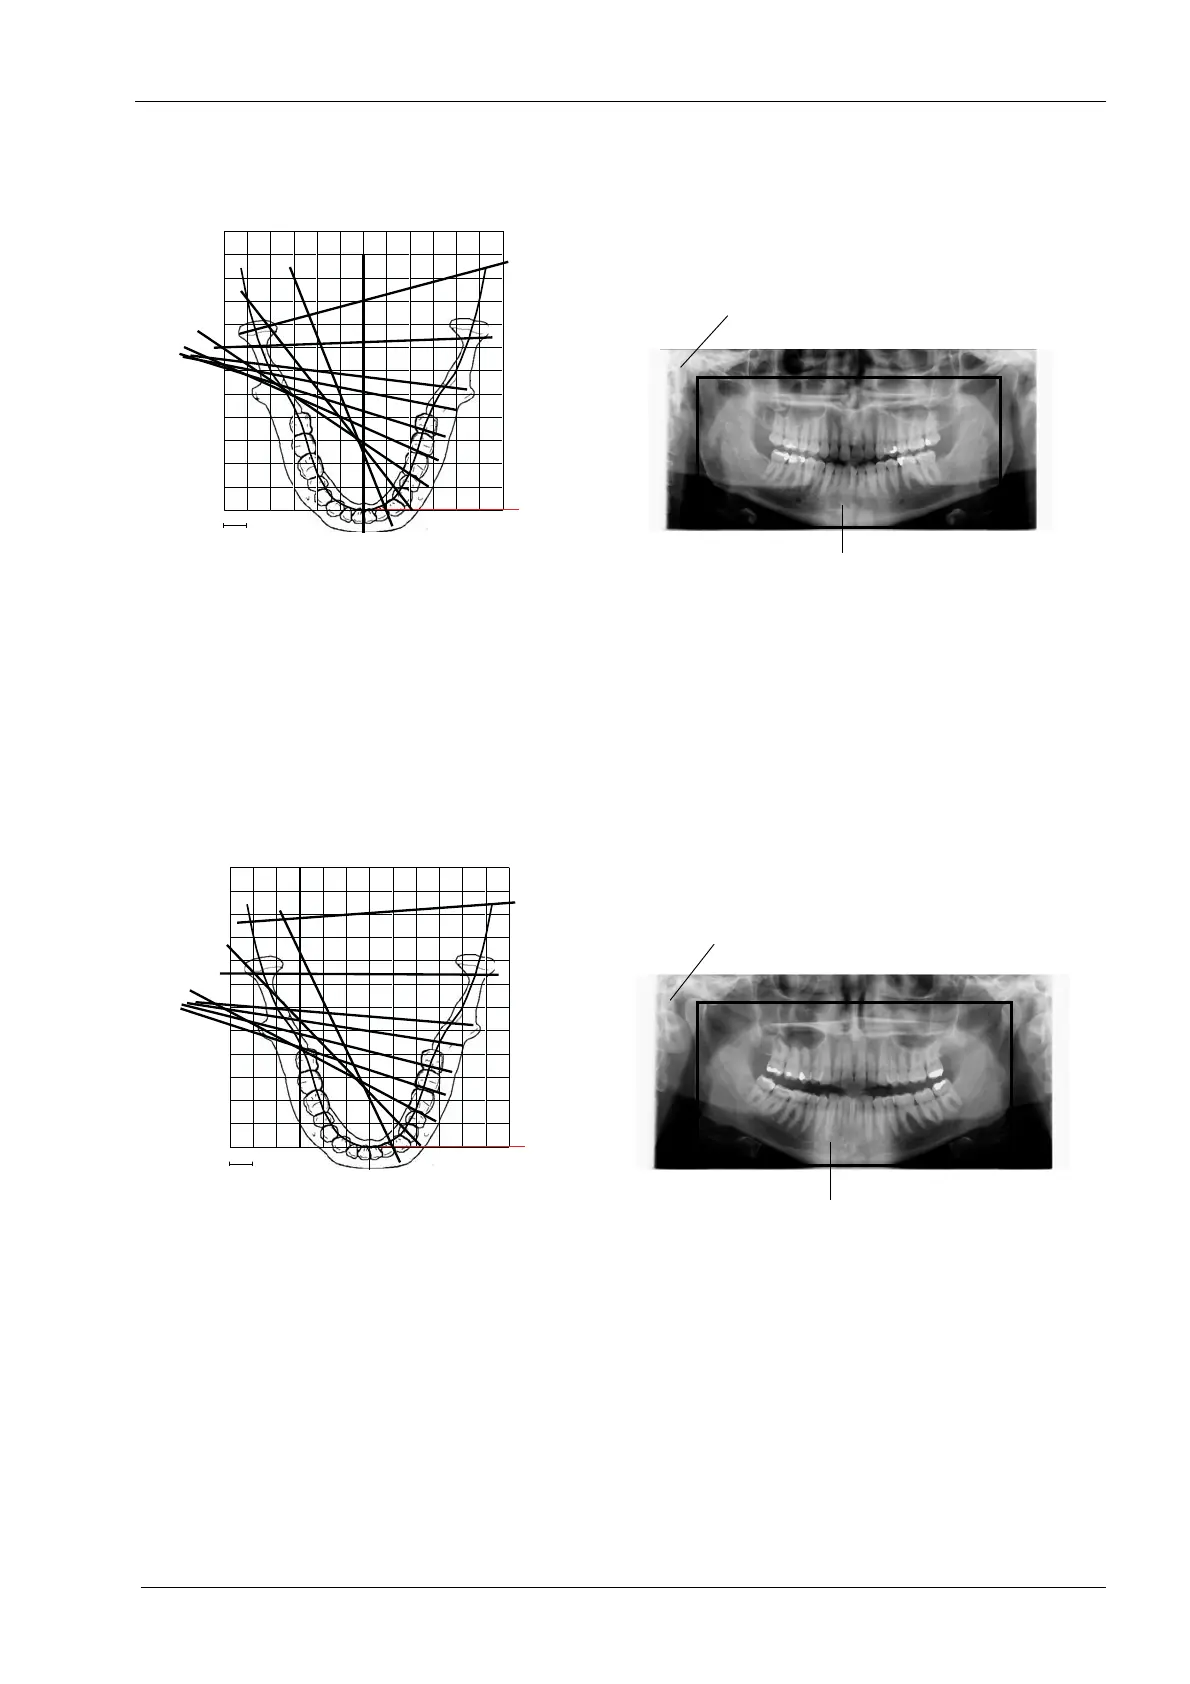

In the Interproximal program the basic imaging geometry

is the same as in the standard panoramic program but the

angle of the X-ray beam is more parallel to the

interproximal contacts of the teeth.

This program is used for caries detection.

NOTE

This program is optimized for interproximal imaging and a

shadow of the opposite side teeth may therefore be visible

in the radiograph.

In the Orthogonal program the basic imaging geometry is

the same as in the standard panoramic program but the

angle of the X-ray beam is more perpendicular to the jaw.

This program is useful for periodontal studies.

This program is optimized for orthogonal imaging and a

layer laser beam

1 cm

Direction of beam

Interproximal panoramic program

Image size for adult setting

Image size for child setting

Orthogonal panoramic program